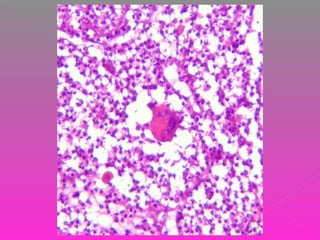

 COLON DERECHO QUE MIDE 20 CM DE

LONG, EL ILEON TERMINAL MIDE 10 CM Y

EL APÉNDICE CECAL 9 CM DE LONG. SE

OBSERVA DILATACIÓN A NIVEL DE LA

VÁLVULA ILEOCECAL DE 10 X 8 CM. AL

CORTE LA PARED ESTÁ ENGROSADA Y

MIDE 1 CM DE ESPESOR, LOS PLIEGUES DE

LA MUCOSA ESTÁN BORRADOS.

 LA RESECCIÓN SEGMENTARIA DE ILEON

MIDE 68 CM DE LONG. LA SEROSA

MUESTRA LESIONES BLANCAS

MILIMÉTRICAS Y A 0.6 CM DEL LÍMITE

QUIRÚRGICO SE IDENTIFICA UNA

CONSTRICCIÓN DE LA LUZ. LOS LÍMITES

QUIRÚRGICOS ESTÁN LIBRES DE LESIÓN

( A 6 CM ) EL EPIPLÓN MIDE 20 CM Y

PRESENTA UN NÓDULO DE 2 CM DE

DIÁMETRO.

 TUBERCULOSIS INTESTINAL Y PERITONEAL